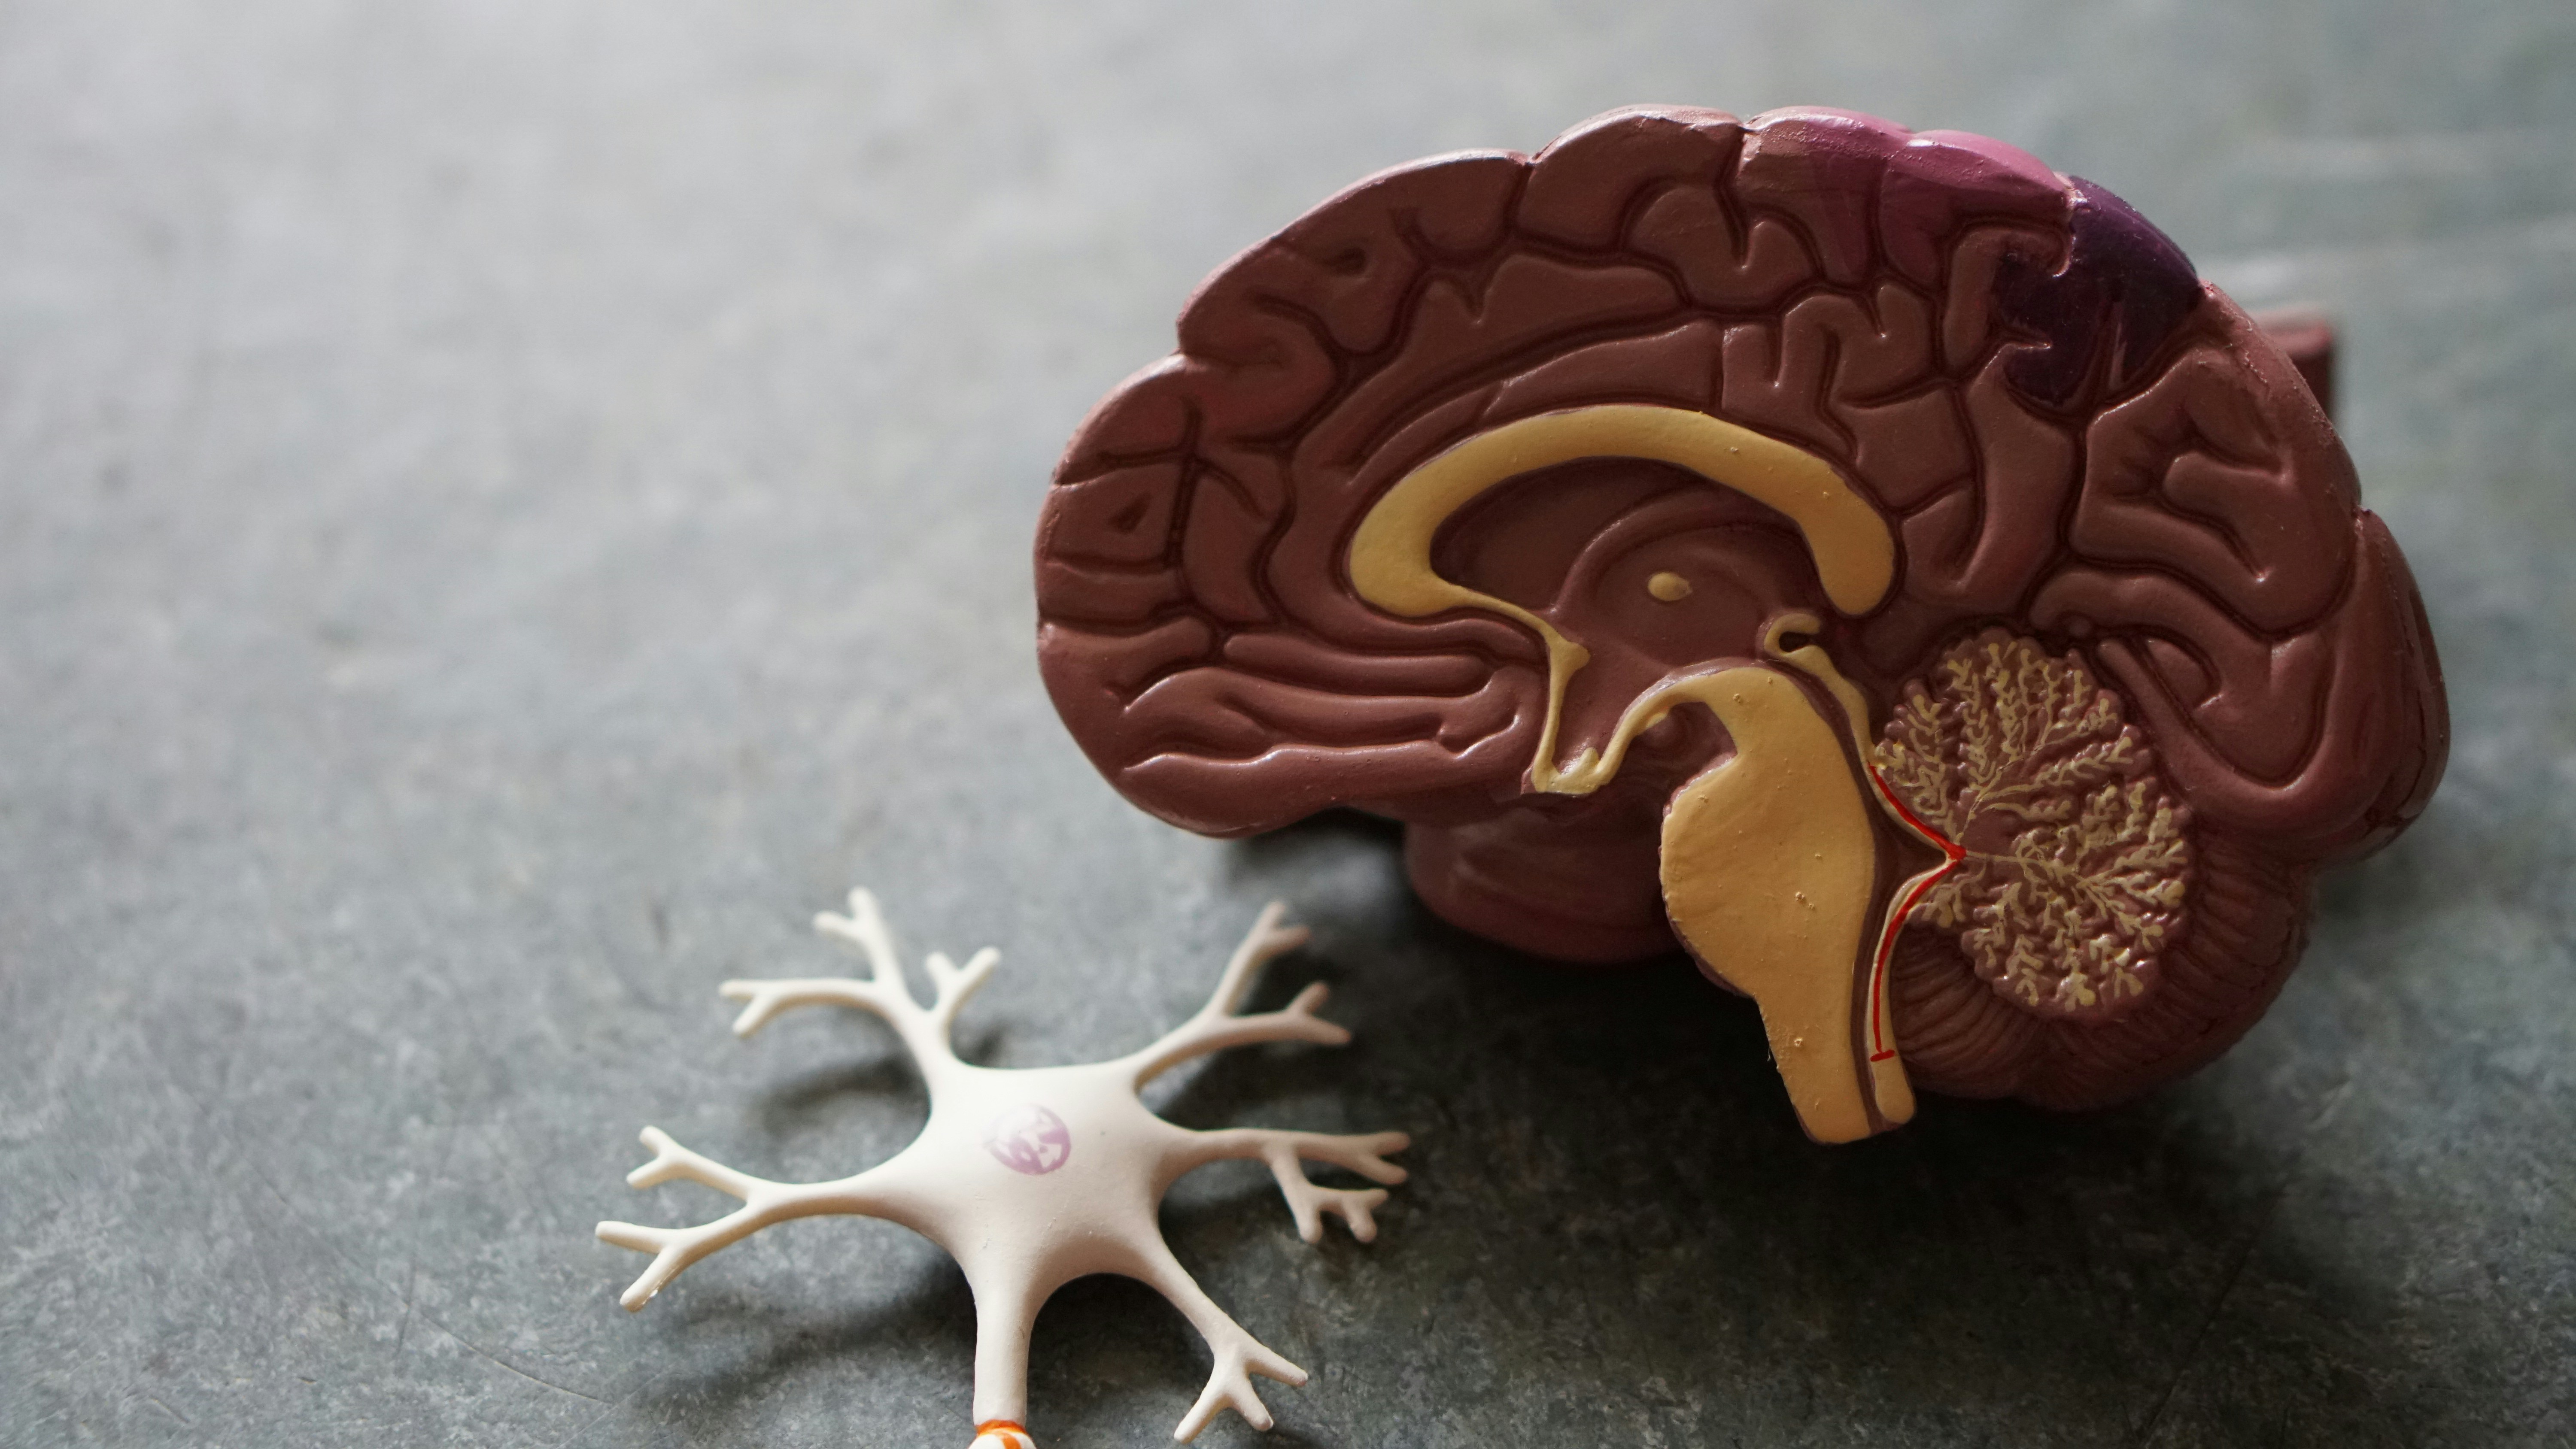

This image is property of images.unsplash.com.